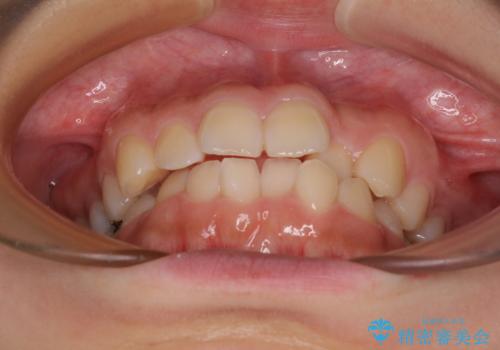

- 前歯のクロスバイトと口元の膨らんだ横顔の印象を気にして来院された患者様です。

レントゲン写真の分析結果からは、それほど口元が突出しているという結果にはなりませんでした。

しかしながら、唇を閉じたときに口元に緊張感があり、そのまま叢生を解消すると横顔が突出した印象になる可能性が高かったため、上下左右の小臼歯4本を抜歯して、ワイヤー装置にて矯正治療を行うこととしました。